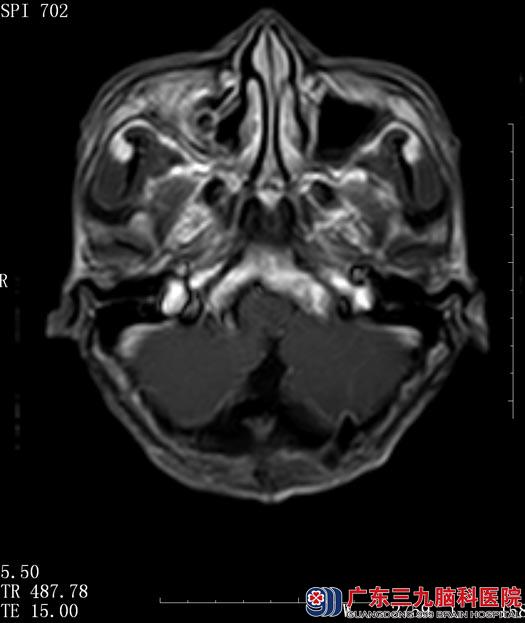

广东三九脑科医院核磁共振检查结果:“右侧小脑半球囊实性占位,实性部分直径约2cm,考虑血管母细胞瘤”。

综合神经外科鲁明主任阅片后认为:结合患者病史、症状、体征及头颅MR检查,考虑右侧小脑半球血管母细胞瘤,肿瘤呈囊实性,对小脑半球及脑干有压迫,手术指征明确。

▲手术前